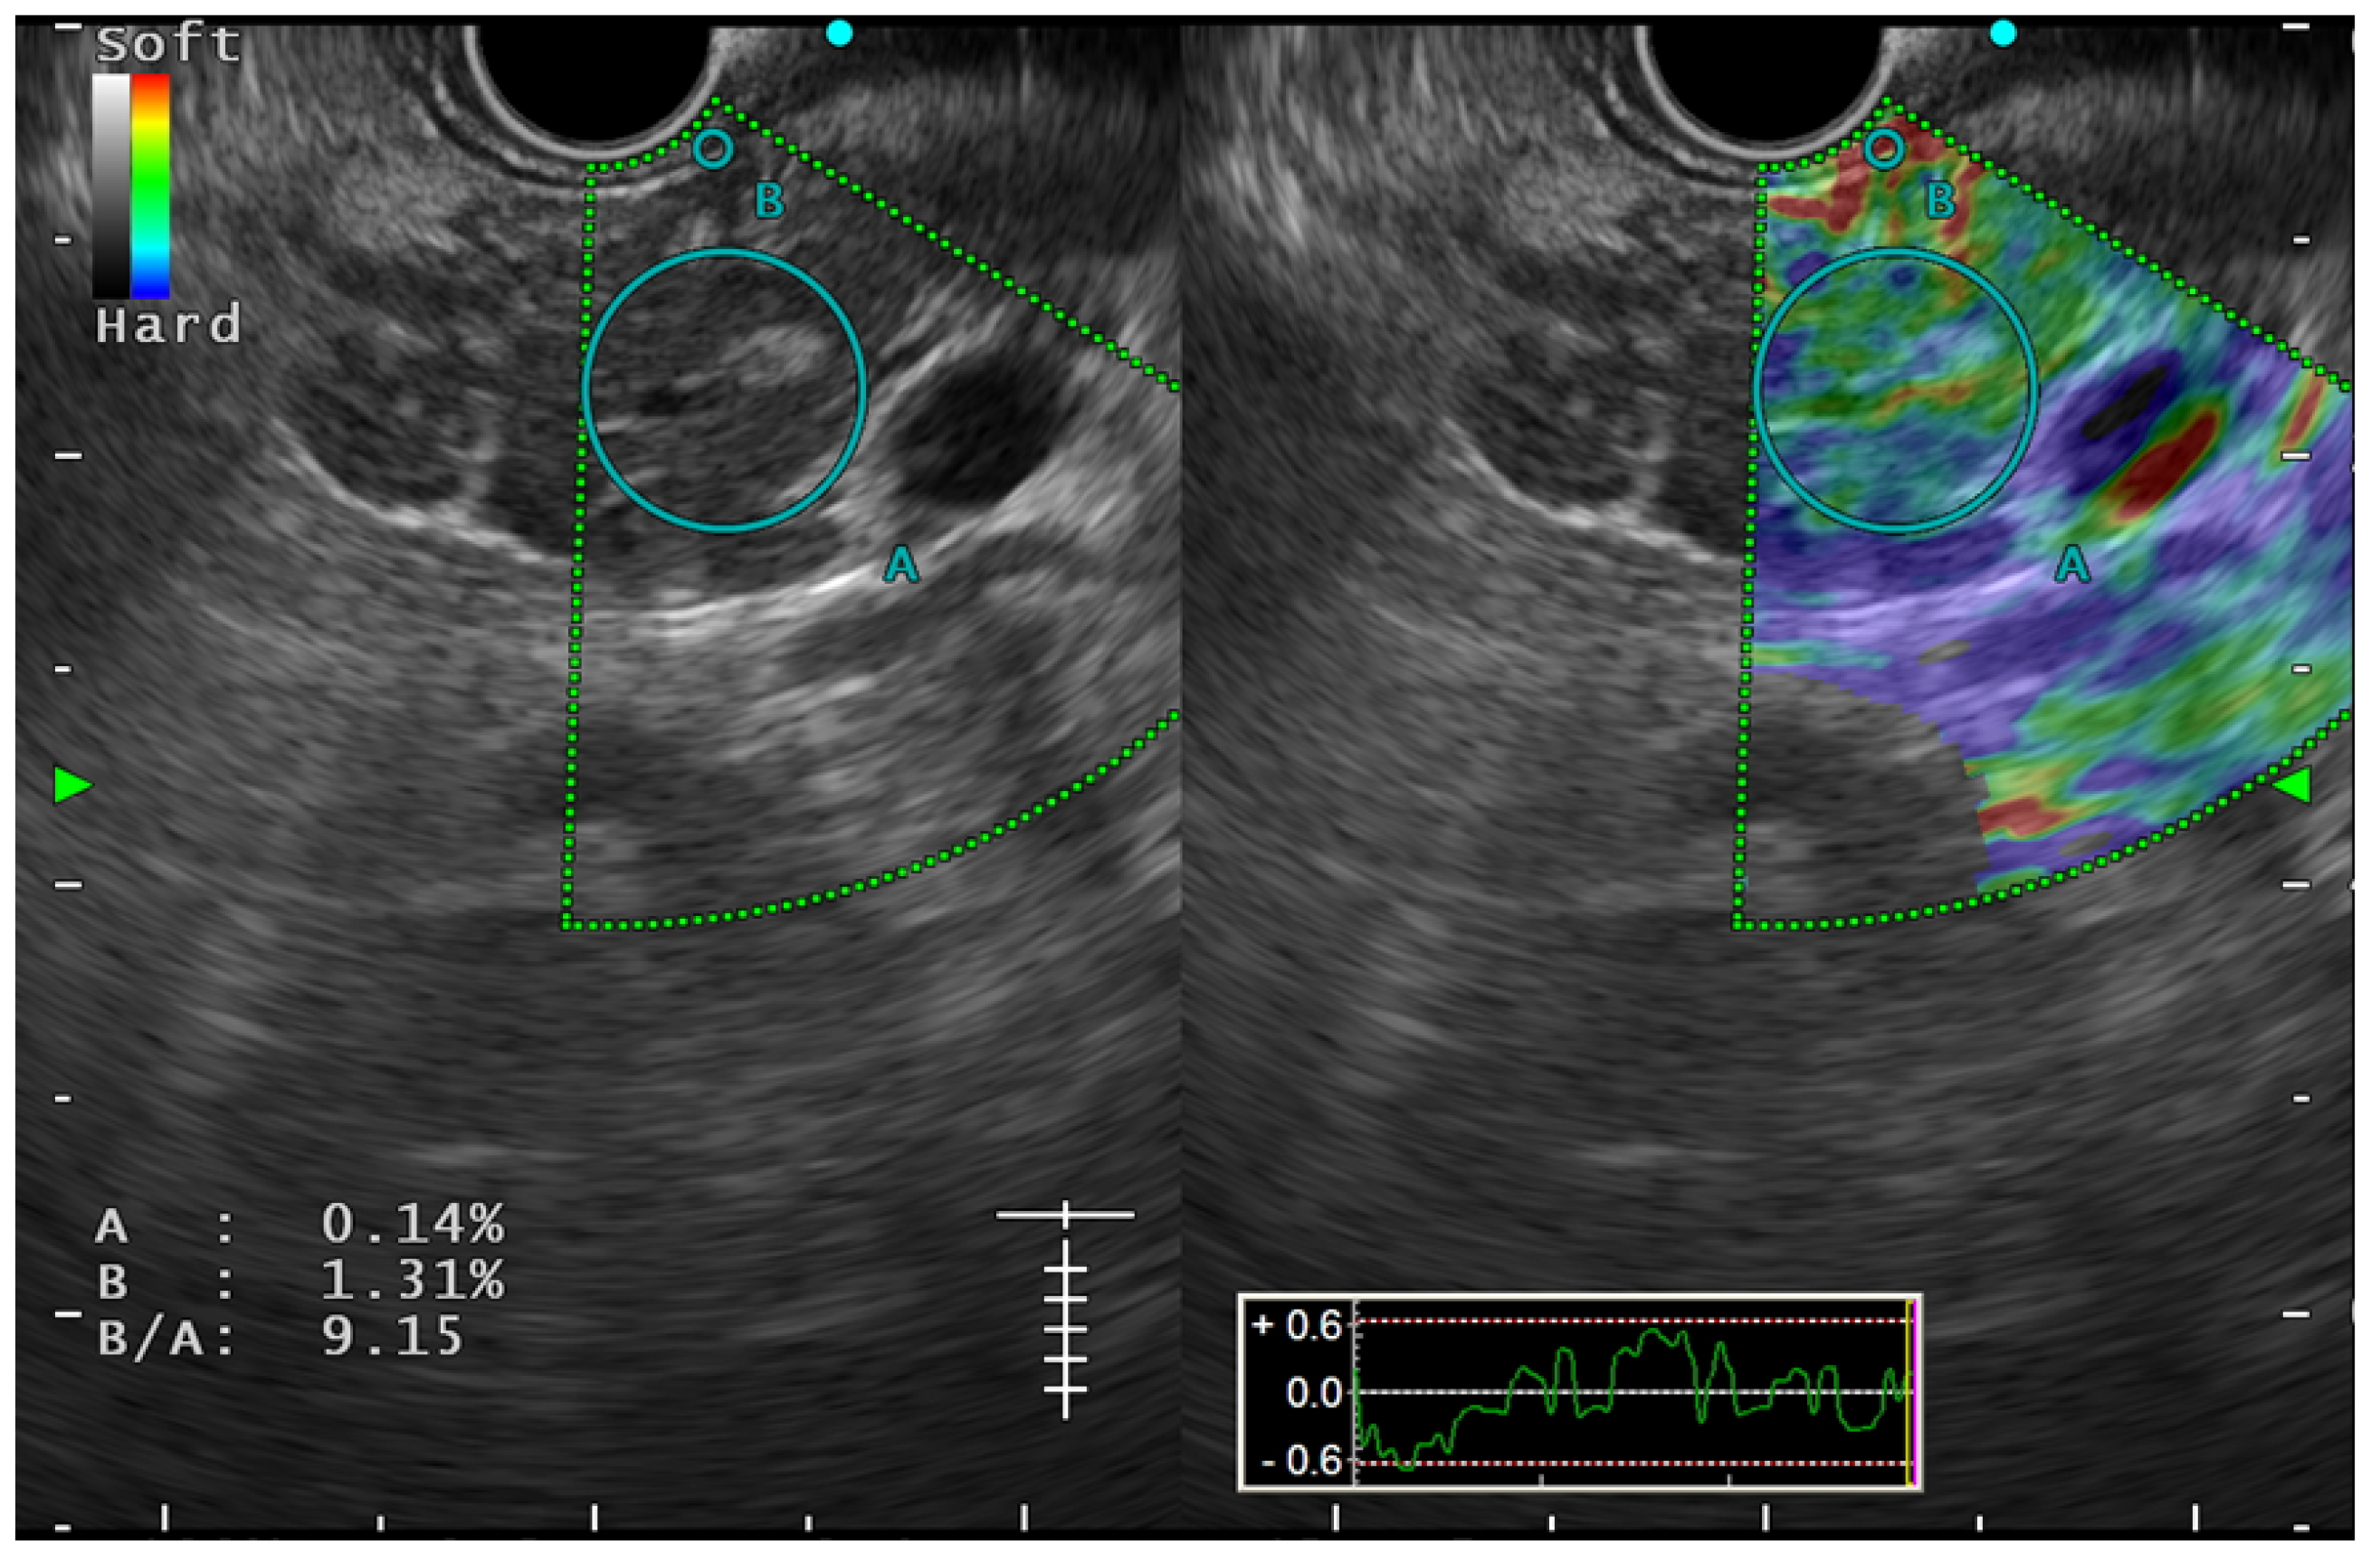

6.3. The Role of EUS Elastography in Early CP